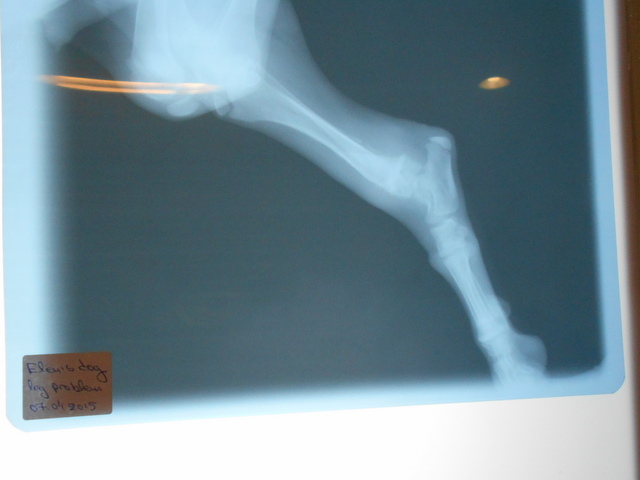

| Noch ein junger Hund - JASPER - wurde von einem Auto angefahren und hat ein gebrochenes Beinchen, das der Tierarzt auf Zypern nicht operieren kann. Die Tierarzthelferin hat sich schützend vor ihn gestellt, damit er nicht eingeschläfert wird und nun lebt er in einem kleinen Käfig. Wir möchten die Operationskosten für Jasper gerne übernehmen und auch hierzu benötigen wir dringend Ihre Hilfe, damit Jasper bald operiert werden kann, bevorzugt in Deutschland. Jasper sucht auch noch ein endgültiges Zuhause bzw. eine liebevolle Pflegestelle in der er genesen kann. |